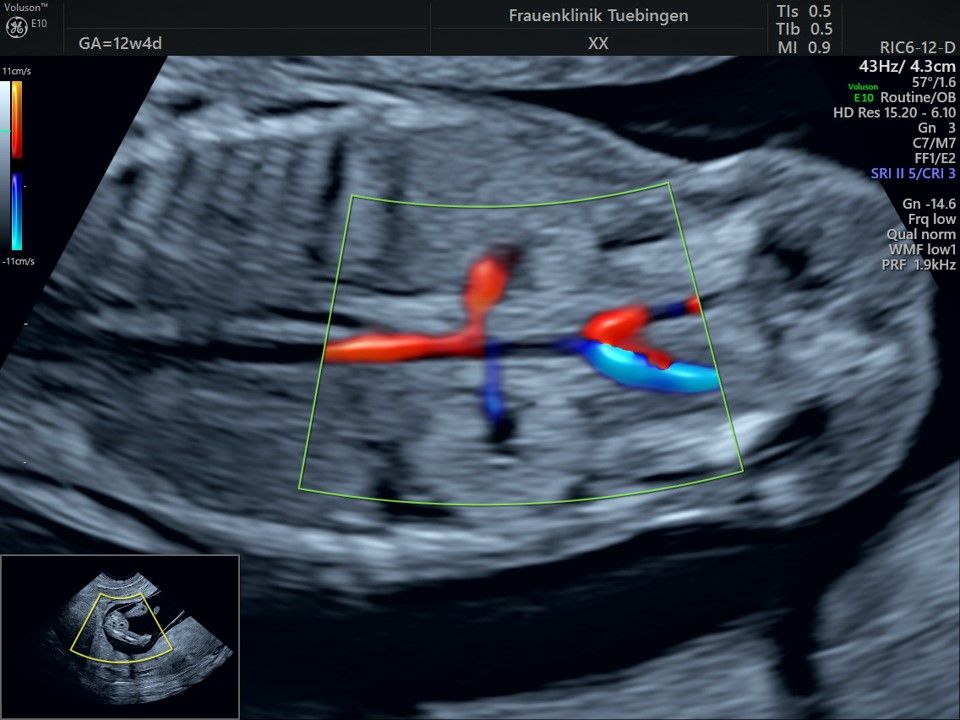

Das Ergebnis der Ultraschalluntersuchung ist wegweisend. Dabei wird der Fet vermessen, die Organe werden untersucht und die sonographischen Marker zur Risikoberechnung für Chromosomenstörungen werden beurteilt. Das sind: die Nackentransparenzdicke, Nasenbein sowie der Blutfluss in der rechten Herzhälfte und im Ductus venosus, einem Gefäß in der Leber des Feten.

Mithilfe des Ersttrimester-Screenings kann das persönliche Risiko einer Präeklampsie bestimmt werden. Dazu wird die Vorgeschichte der Schwangeren, der aktuelle Blutdruck, das Ergebnis der Ultraschalluntersuchung (Widerstand in den Gebärmutter-nahen Gefäßen) und der Blutabnahme bei Ihnen (PAPP-A) kombiniert. Sollte das Risiko über 1:100 sein, empfehlen wir die tägliche Einnahme von Aspirin 150mg bis zu 35.SSW und eine gezielte Überwachung der weiteren Schwangerschaft.